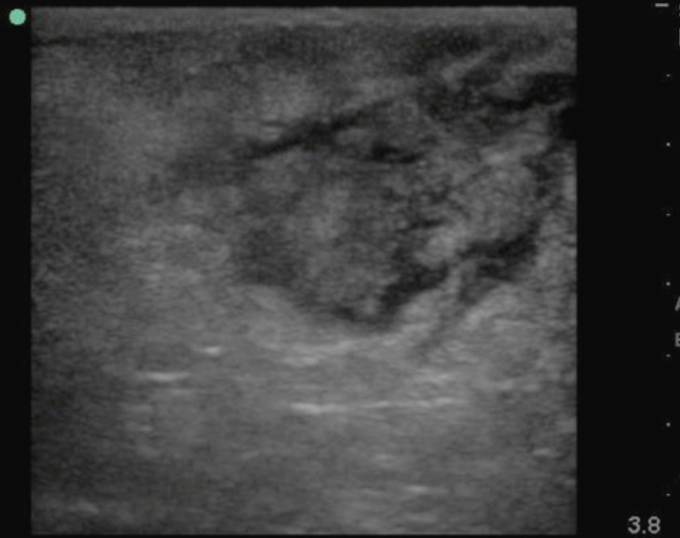

- Soft tissue ultrasound can differentiate between abscess and cellulitis

- Assess for fluid collection and swirl within the collection